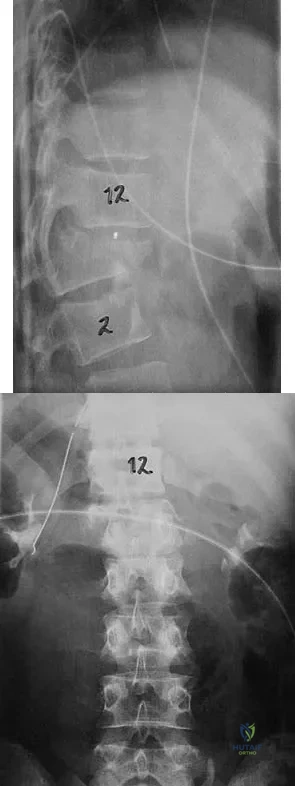

Figures 27a and 27b show the radiographs of a 32-year-old woman who was involved in a high-speed motor vehicle accident. She is neurologically intact. After stabilization and assessment, treatment should consist of

Explanation

The radiographs show a fracture-dislocation with translation in both the coronal and sagittal planes, evidence of significant instability requiring surgical stabilization. Anterior instrumentation is not as effective as posterior instrumentation in restoring stability, and because there is little bony destruction, the anterior column can be successfully reconstructed with simple realignment. The treatment of choice is multisegment posterior fusion with instrumentation. Lewandrowski KU, McLain RF: Thoracolumbar fractures: Evaluation, classification, and treatment, in Frymoyer JW, Wiesel SW (eds): The Adult and Pediatric Spine. Philadelphia, PA, Lippincott Williams and Wilkins, 2004, pp 817-843.